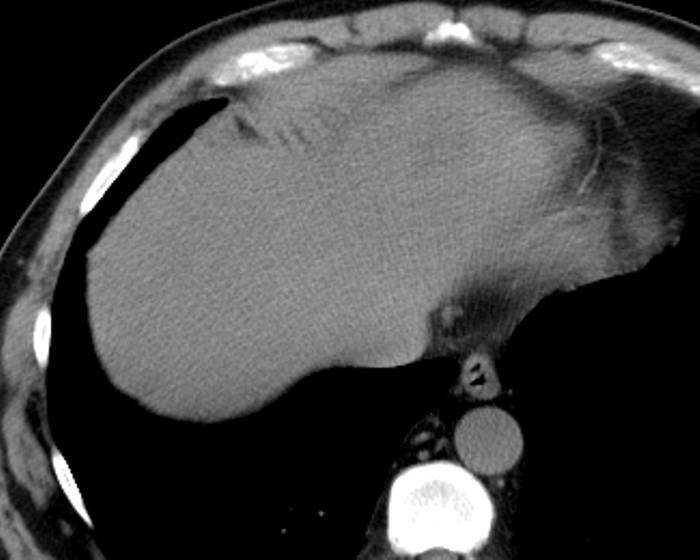

Ung thư đường mật

» Thông tin: Nam giới – 57 tuổi.

» Lâm sàng: Đau bụng.